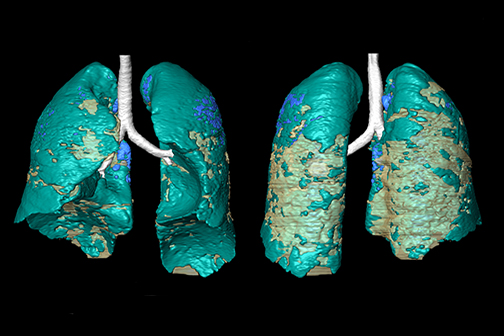

LSU Health New Orleans Study Reports Compound Blocks SARS-CoV-2 and Protects Lung Cells

Research conducted at LSU Health New Orleans Neuroscience Center of Excellence reports that Elovanoids, bioactive chemical messengers made from omega-3 very-long-chain polyunsaturated fatty acids discovered by the Bazan lab in 2017, may block the virus that causes COVID-19 from entering cells and protect the air cells (alveoli) of the lung. More